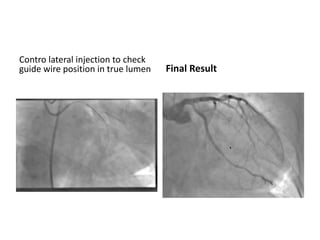

Contro lateral injection to check

guide wire position in true lumen Final Result